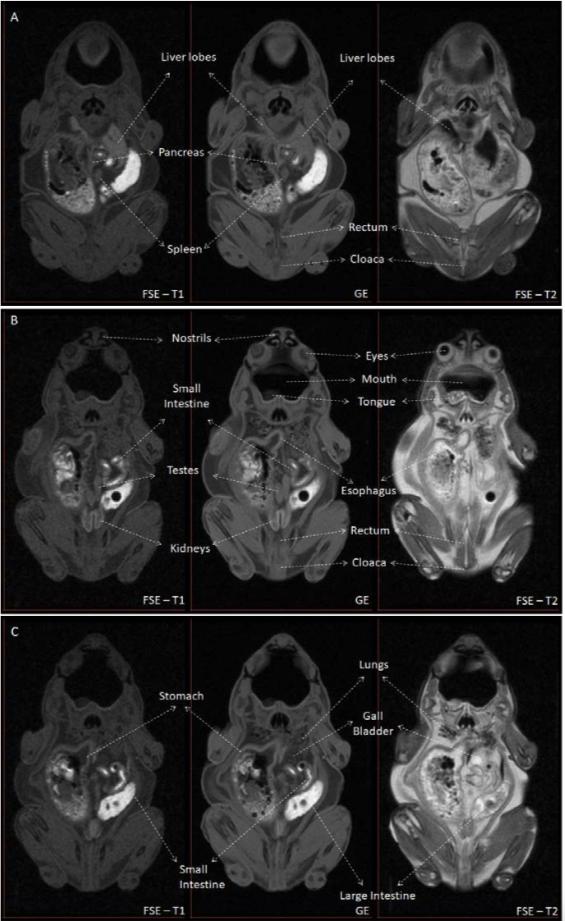

Figure S1 - MRI identification of structures contained in the coelomic cavity. Figure S1 shows the main structures identified in the coelomic cavity in Kaloula pluchra frog. Three different slices of the MRI experiment were selected (A, B, C). Three different MRI weightings (Fast Spin Echo T1-weighted, Gradient Echo and FSE T2-weighted) are shown for each slice.

|